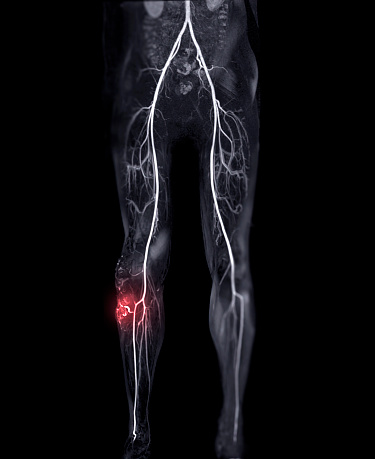

- 동맥 경화: 혈관 내벽에 지방이 쌓여 혈관이 좁아지고 딱딱해지는 질환입니다. 심장 경색, 뇌졸중, 말초 동맥 질환 등의 원인이 됩니다.

- 심혈관 질환: 심장과 혈관에 관련된 질환의 총칭입니다. 심장 경색, 뇌졸중, 협심증, 말초 동맥 질환 등이 여기에 속합니다.